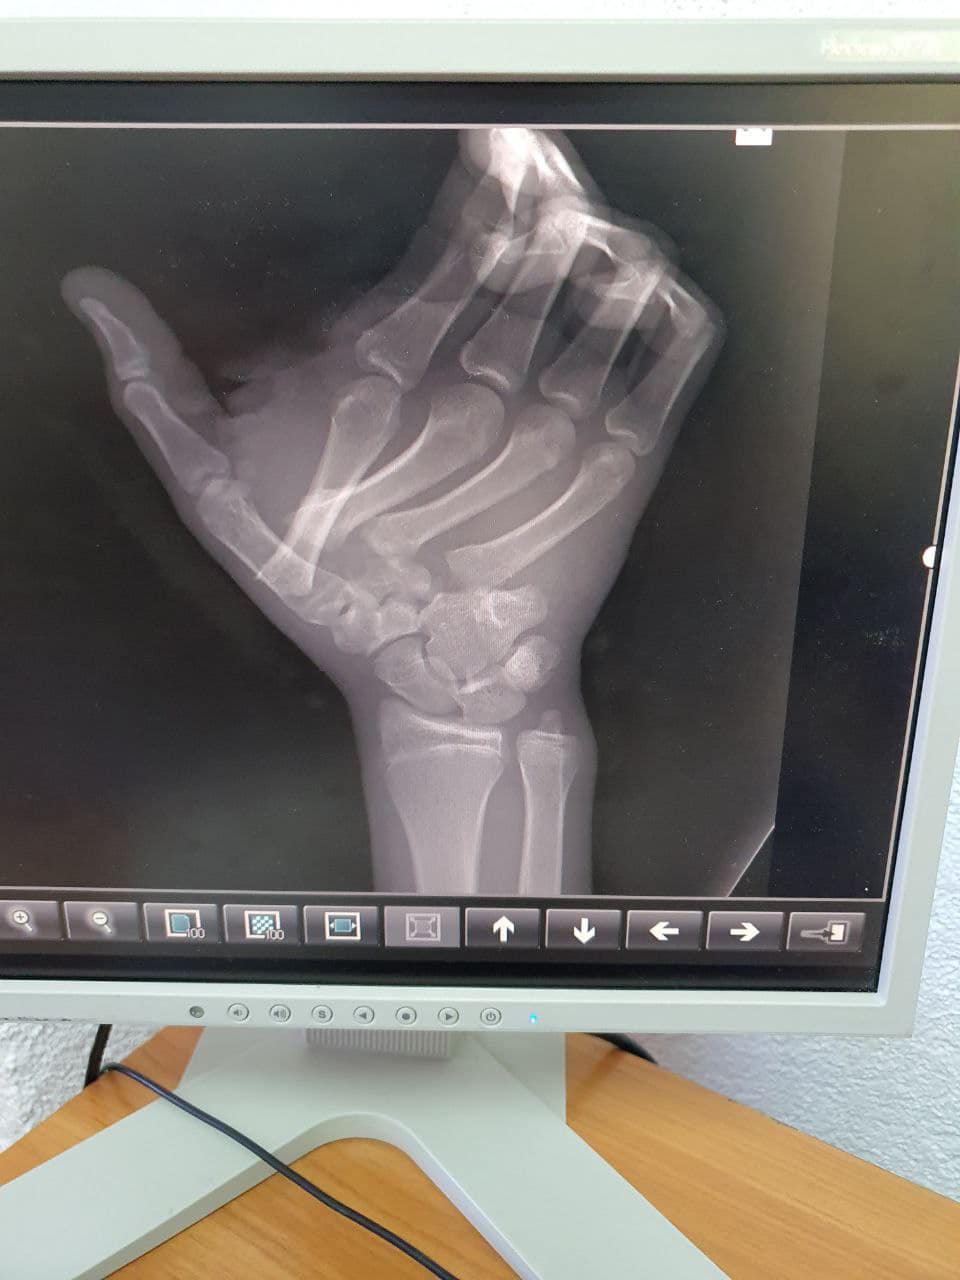

Повідомляється, що хлопець отримав переломи й вивихи декількох кісток зап’ястя і переломи з відкритими рвано-різаними ранами в області першого і другого пальця.

Також зазначається, що пацієнту провели фасціотомію: розрізали сполучну тканину, щоб зняти тиск в кінцівці, і зібрали всі кісточки кисті разом.

Зазначається, що кістки пальців травматологи зафіксували чотирма спицями Кіршнера, які пацієнт носить вже близько місяця.